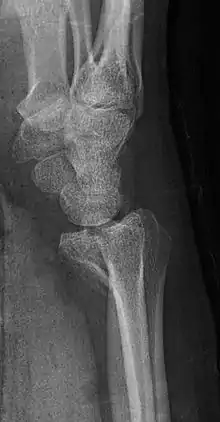

Lateral projectional radiograph of the same fracture

There exist two types of Barton's fracture – dorsal[3] and palmar, the latter being more common. The Barton's fracture is caused by a fall on an extended and pronated wrist increasing carpal compression force on the dorsal rim. Intra-articular component distinguishes this fracture from a Smith's or a Colles' fracture. Treatment of this fracture is usually done by open reduction and internal fixation with a plate and screws, but occasionally the fracture can be treated conservatively.[4]